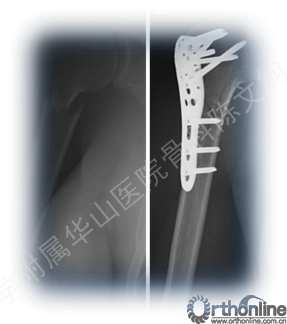

病情描述:患者女性,80岁,因跌倒致右肱骨近端骨折

X光片示:右肱骨近端骨折,NEER 3型

全身麻醉下行右肱骨近端切开复位内固定术

术后X光片示: 复位良好